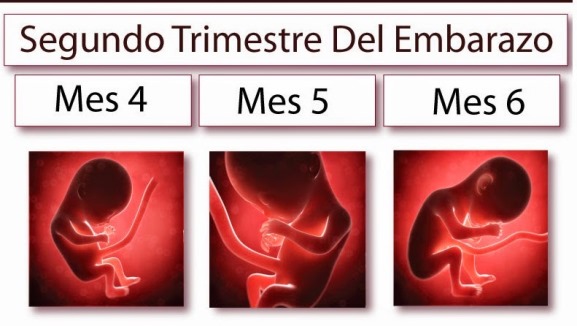

Segundo trimestre

Durante el segundo trimestre, los niveles hormonales se estabilizan y la placenta se encuentra ya formada, por lo que los síntomas tienden a desaparecer y la gestante vuelve a sentirse bien. En esta etapa, el sueño puede verse interrumpido con frecuencia, por la necesidad de orinar o por las primeras molestias circulatorias o digestivas.